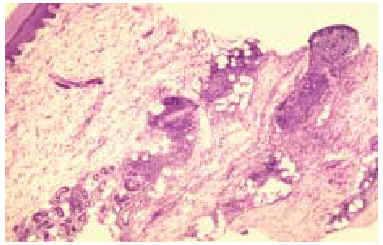

En el estudio histológico de todas las biopsias se observó un infiltrado perivascular en la dermis superficial y profunda compuesto por linfocitos, polimorfonucleares y abundantes eosinófilos (figs. 2 y 3). La intensidad del infiltrado fue variable, siendo muy denso y con un gran número de eosinófilos en los casos 1 y 4, en los que además se observó un marcado edema en la dermis papilar con formación de una ampolla subepidérmica. El resultado del estudio inmunohistoquímico se resume en la tabla 3. En todos los casos existía un claro predominio de los linfocitos T (CD3, CD5) sobre los linfocitos B (CD20, CD79a) (fig. 4), excepto en el caso 1, donde el cociente T/B se igualó. En ninguna de las muestras se demostró positividad para CD23 en los infiltrados dérmicos, con la excepción de un único caso en el que las células CD23 positivas no coexpresaban marcadores B ni CD5.

Fig. 3.--Detalle del infiltrado linfohistiocitario rico en eosinófilos.